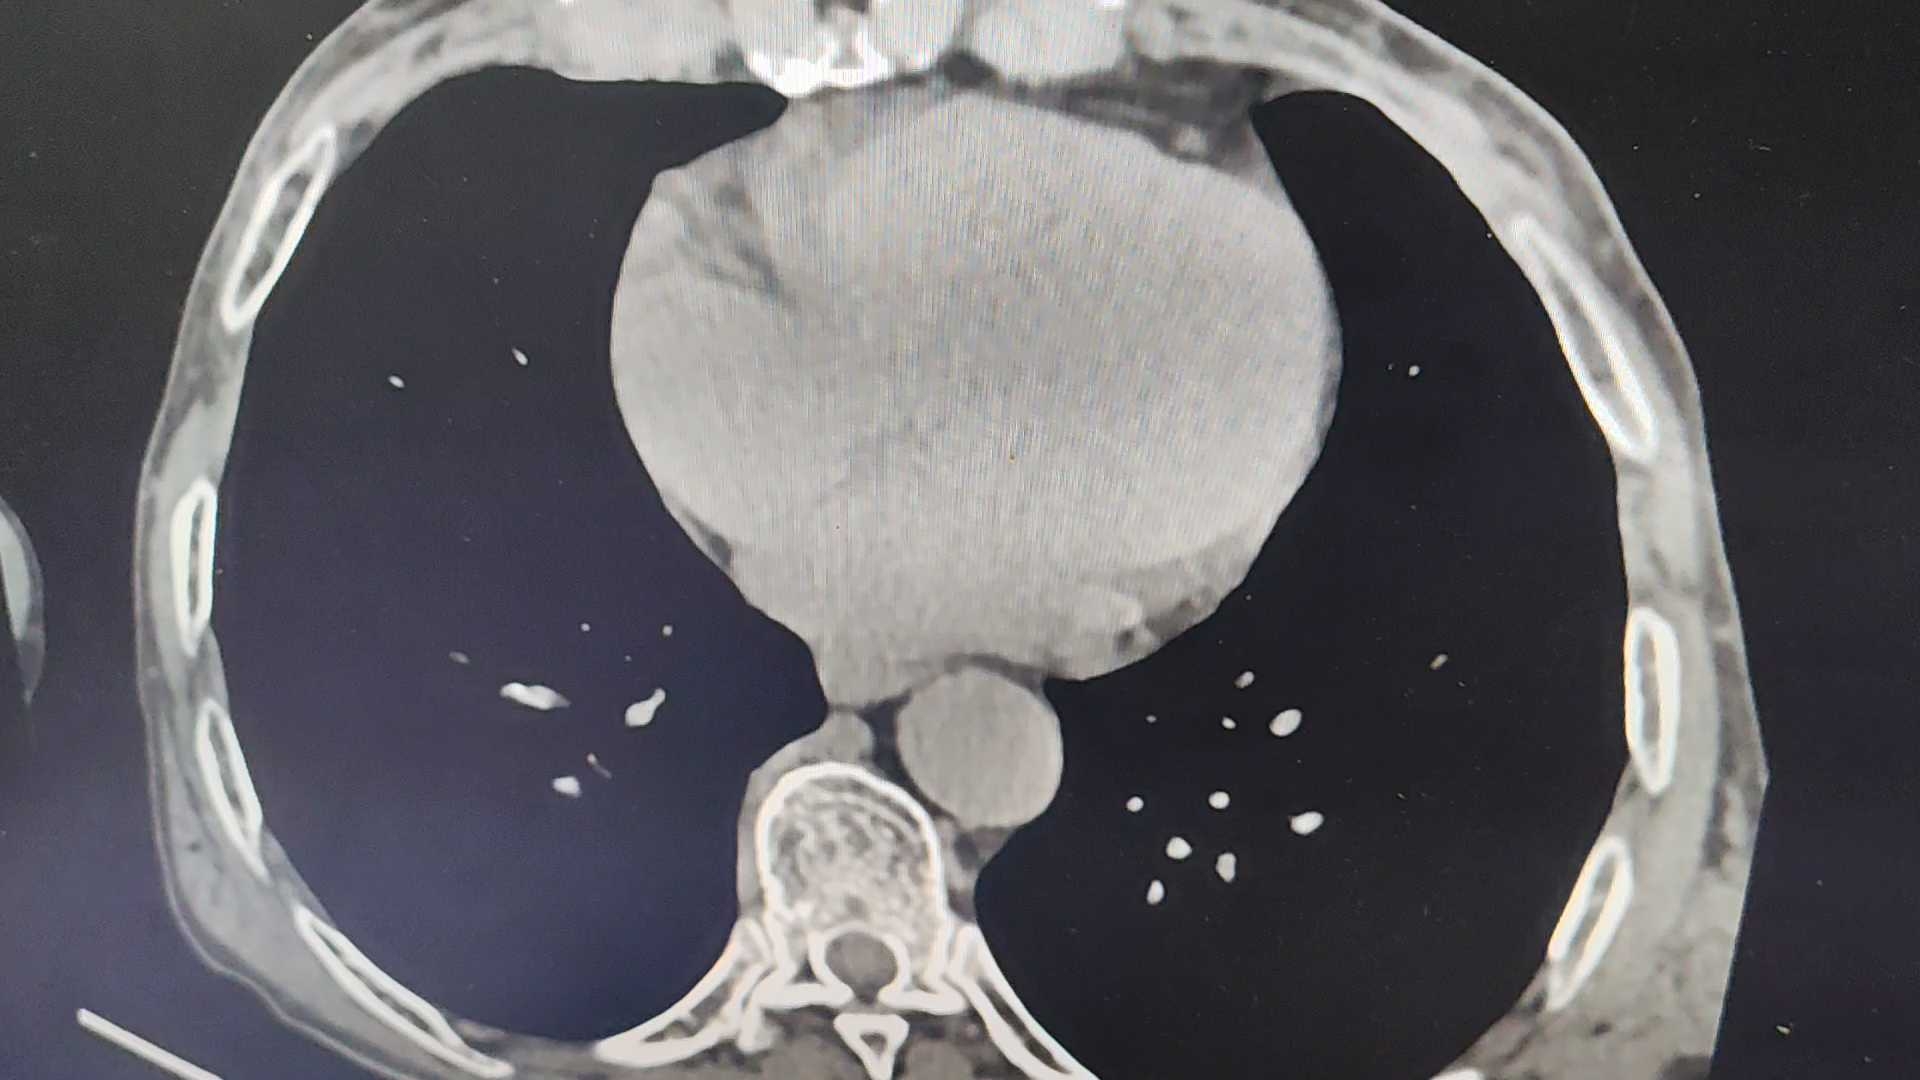

患者,男,80岁,无明显症状,既往无特殊病史,体检查上腹部Ct如下: